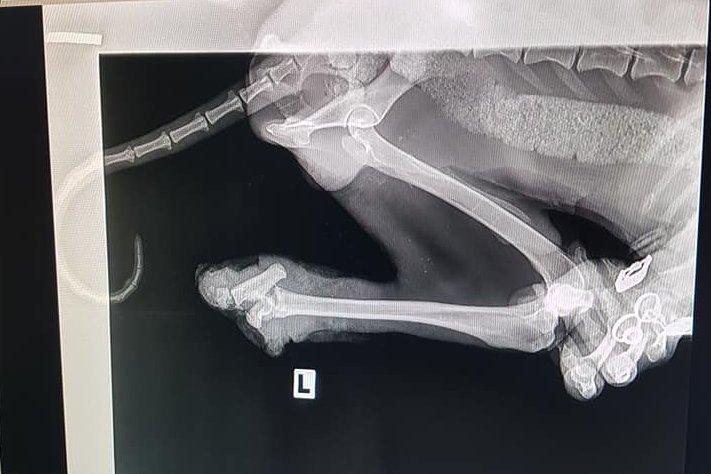

Жестоко насилие над куче край Кърджали. Животното е с отрязани задни крайници и без едно око. То е било намерено до язовир „Студен кладенец“. За щастие на помощ са му се притекли от фондация „Animal Hope Bulgaria“.

От фондацията са го кръстили Лъки-Иван. В социалната мрежа „Facebook“ те публикуваха снимки на кучето и информираха, че вече са храни отлично и излиза на разходка. Добри хора са отворили сърцата си и са дарили за раненото животно сумата от 1120,72 лева. За момента от фондацията спират събирането на средства. Те са необходими са операциите на краката на Лъки-Иван, които трябва да бъдат назначени днес, както и за закупуването на протези.